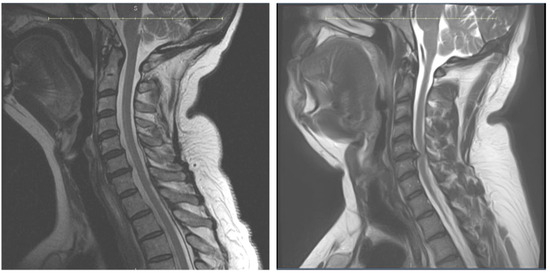

6.3. Advanced Imaging and Diagnostic Tests

- He, B.; Sheldrick, K.; Das, A.; Diwan, A. Clinical and Research MRI Techniques for Assessing Spinal Cord Integrity in Degenerative Cervical Myelopathy—A Scoping Review. Biomedicines 2022, 10, 2621. [Google Scholar] [CrossRef] [PubMed]

- Martin, A.R.; Tetreault, L.; Nouri, A.; Curt, A.; Freund, P.; Rahimi-Movaghar, V.; Wilson, J.R.; Fehlings, M.G.; Kwon, B.K.; Harrop, J.S.; et al. Imaging and Electrophysiology for Degenerative Cervical Myelopathy [AO Spine RECODE-DCM Research Priority Number 9]. Glob. Spine J. 2022, 12, 130S–146S. [Google Scholar] [CrossRef]